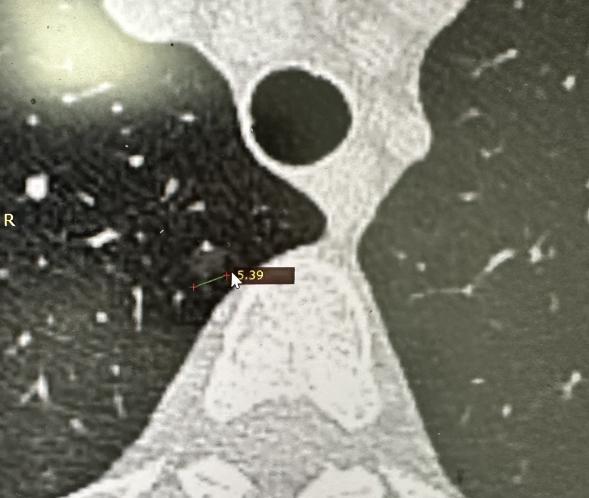

门诊被“肺结节”患者问到最多的6个问题,今天一次性解答!1、吃什么能够消肺结节?

打破谣言!肺结节大于8mm就一定要手术吗?最近这段时间,不管是网上的网友留言,还

肺结节随访观察期间,会不会突然变大、变得危险?很多患者听我说建议随访,都会特别焦

“医生,您说我这个肺结节考虑是微浸润癌,那大概多久会变成浸润癌?”这是我在门诊中

关于肺结节,医生的很多诊断表述看似委婉,其实藏着明确的健康信号,这些“暗语”你能

很多人会担心,肺结节做了手术之后,会不会刺激结节继续生长,或者长出新的结节?

1A期肺癌的病理报告上,却出现了“低分化”三个字,这到底意味着什么?经常有患者朋

4种早期肺癌,术后复发率极低,可放心!并非所有肺癌术后都要提心吊胆,医学研究进一